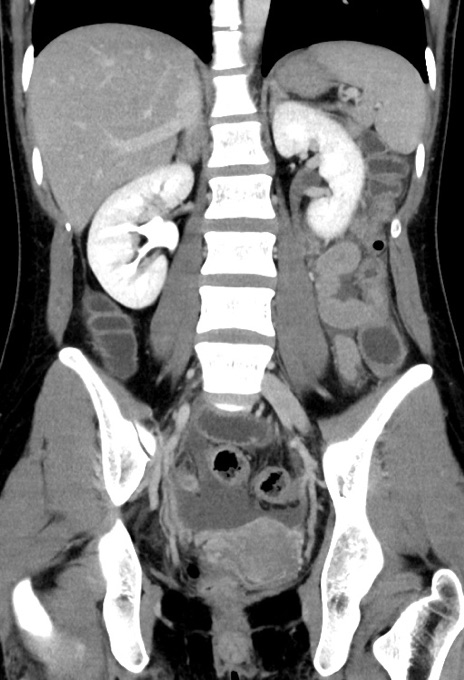

症例17(冠状断像)

【症例】20歳代女性

【主訴】嘔吐、下腹部痛

【現病歴】昨日夕食後に嘔吐し下腹部痛が出現。本日になっても嘔吐持続し改善しないため来院。

【身体所見】意識清明、BT 37.2℃、BP 108/67mmHg、腹部:平坦、やや硬、下腹部正中から右にかけて圧痛あり、反跳痛軽度あり、tapping pain(+)。

【データ】WBC 13600、CRP 14.94